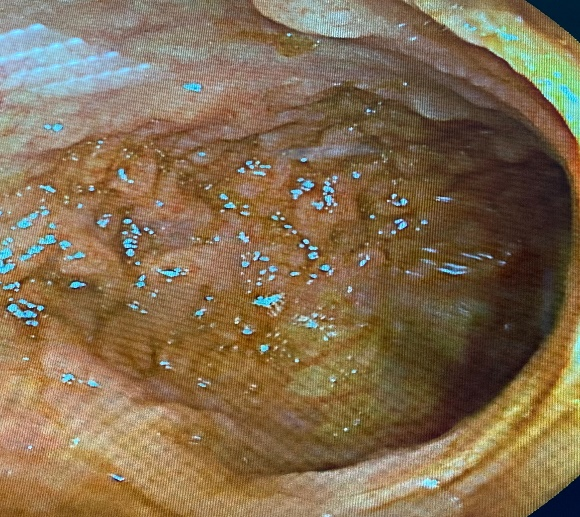

1. On eso-gastro-duodenal fibroscopy: erythematous petechial gastric mucosa with multiple polyps of different ages and sizes, the largest of which are around 1 cm, biopsies were taken (Figure 1).

Figure 1 Gastric polyps.